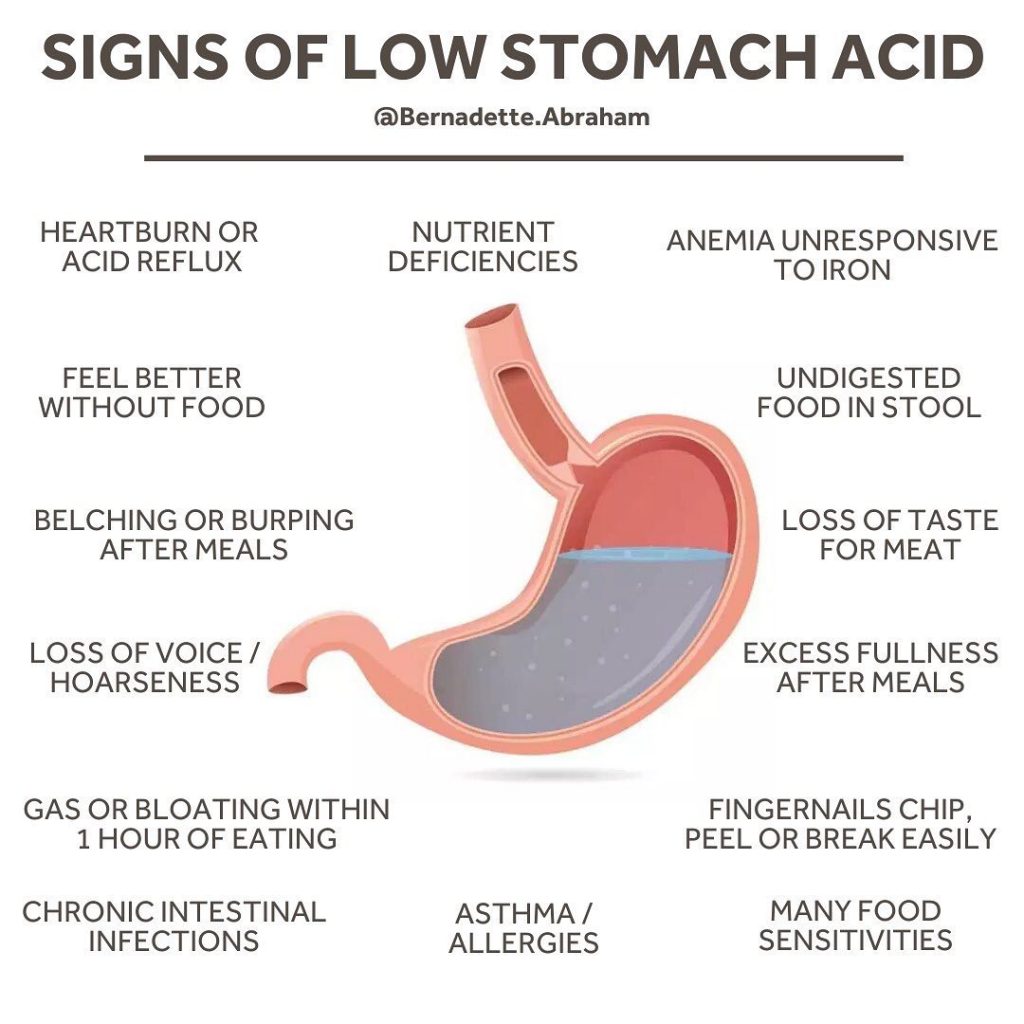

The Importance of Stomach Acid – Bernadette Blog

Pin on Holistic & Spiritual Health

Pin on Healthy Lifestyle

Pin on Natural Remedies

Alkaline-Forming Foods Avoid Acid Eflux, Heartburn, GERD And Barrett’s …